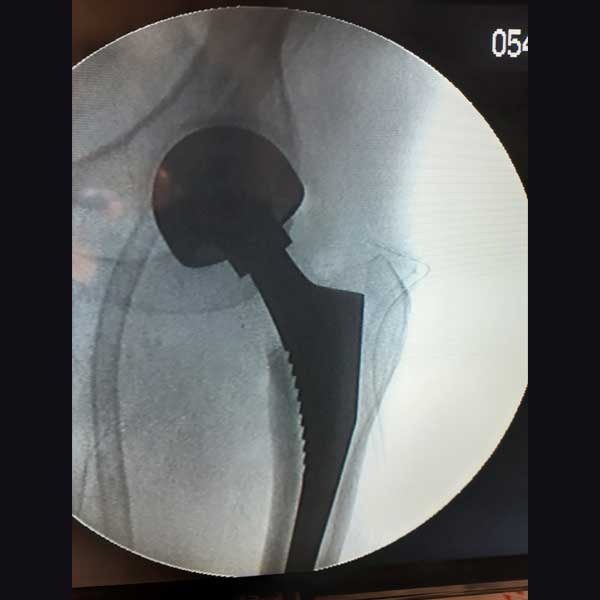

Case 1 - Hip Hemiarthroplasty

A female patient, aged 72 years. She had been diagnosed to have a Closed fracture of neck Fracture. She was treated operatively with Hip Hemiarthroplasty.

Immediate Post-Operative